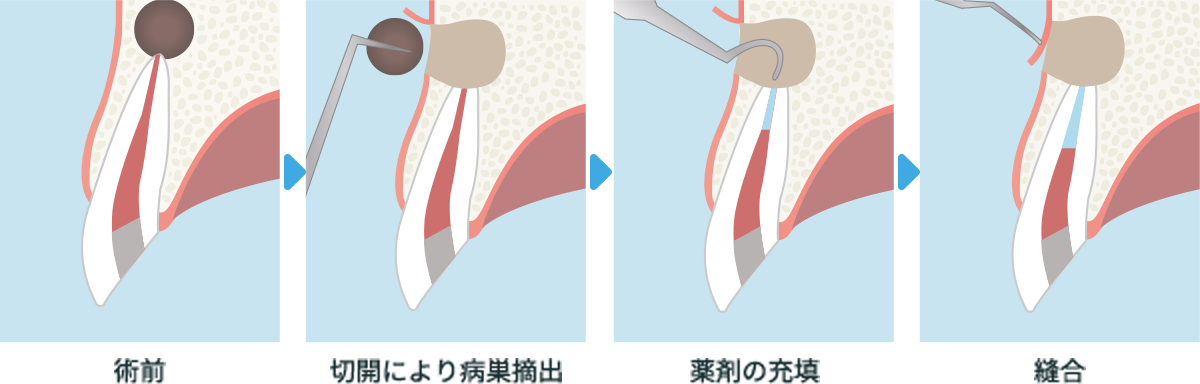

歯根端切除術

根管の根っこに病巣が発生して、根管治療後症状が改善しない場合や病巣が大きく、根管治療では不十分と診断した場合に外科手術で摘出します。病巣切除後は薬剤を充填し、清潔な状態にして縫合します。

横スクロールで確認いただけます。